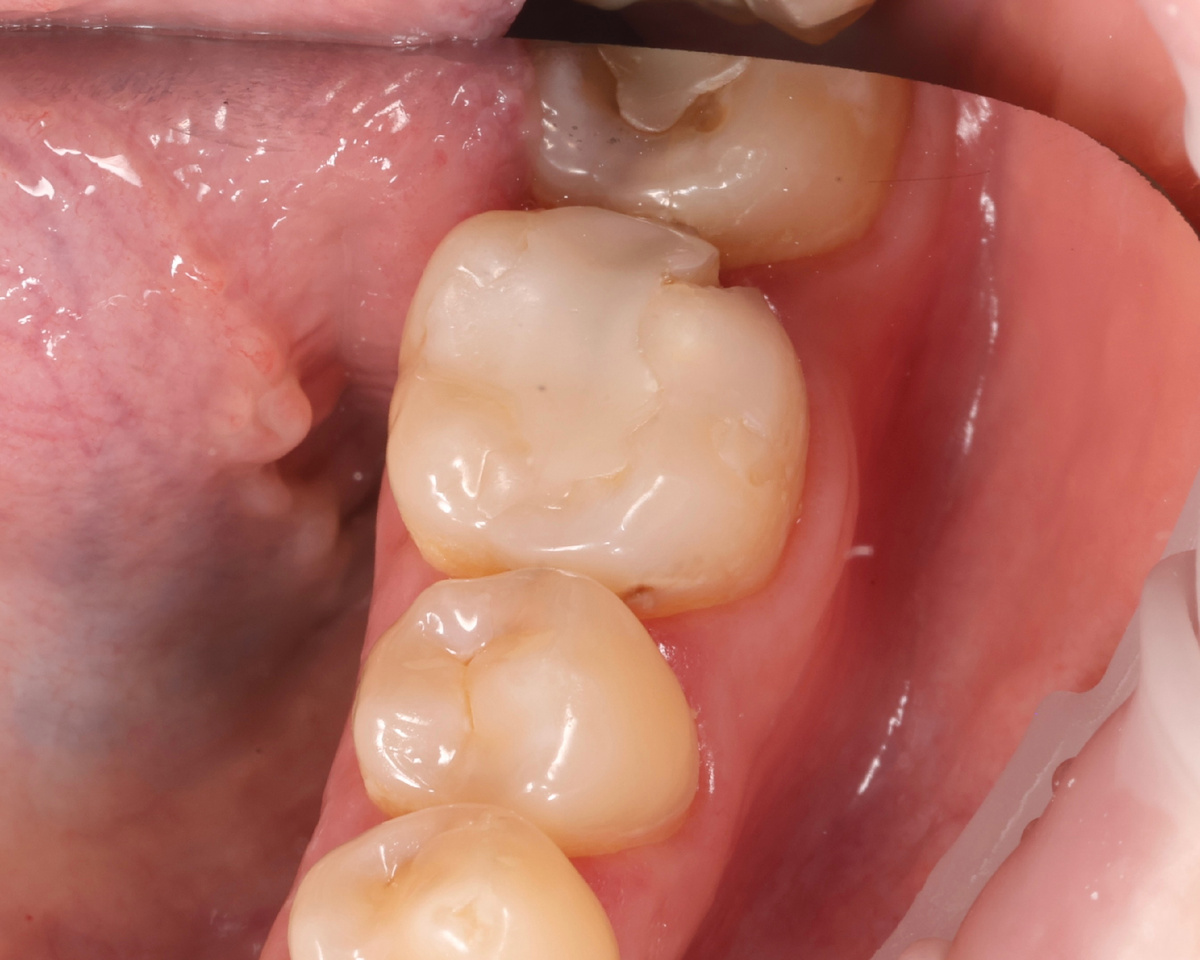

Готовая работа